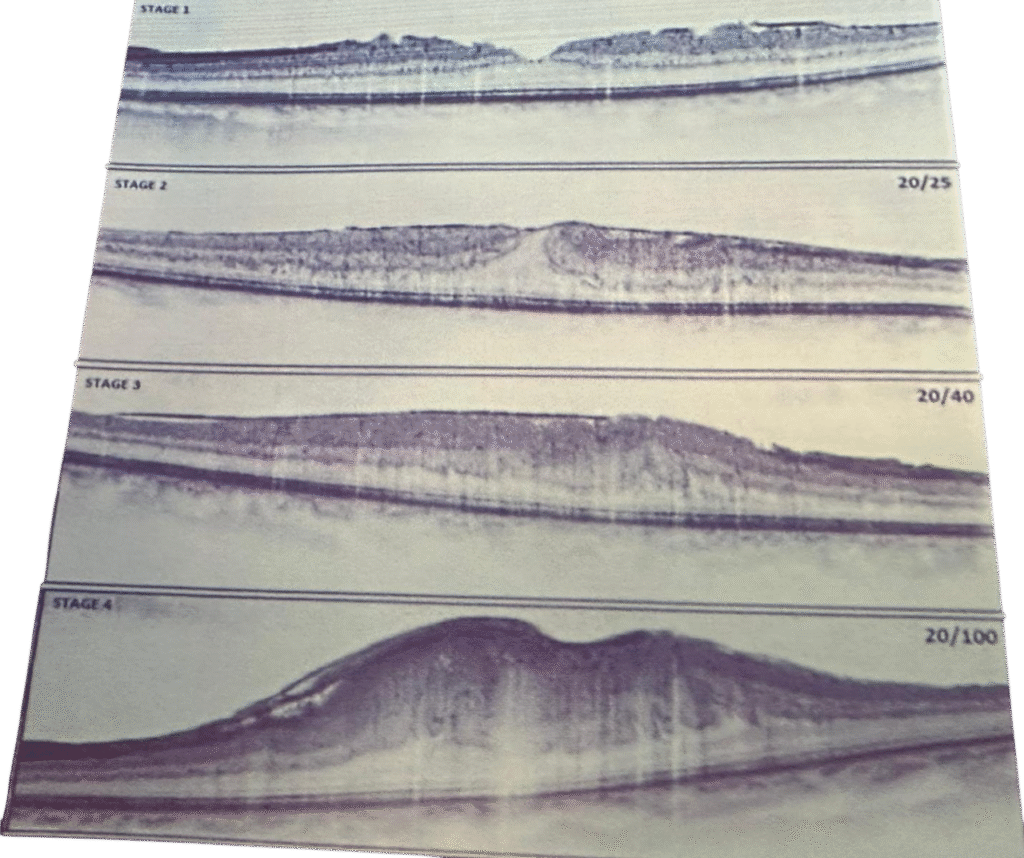

Resim 3: Epiretenal genel görünümü